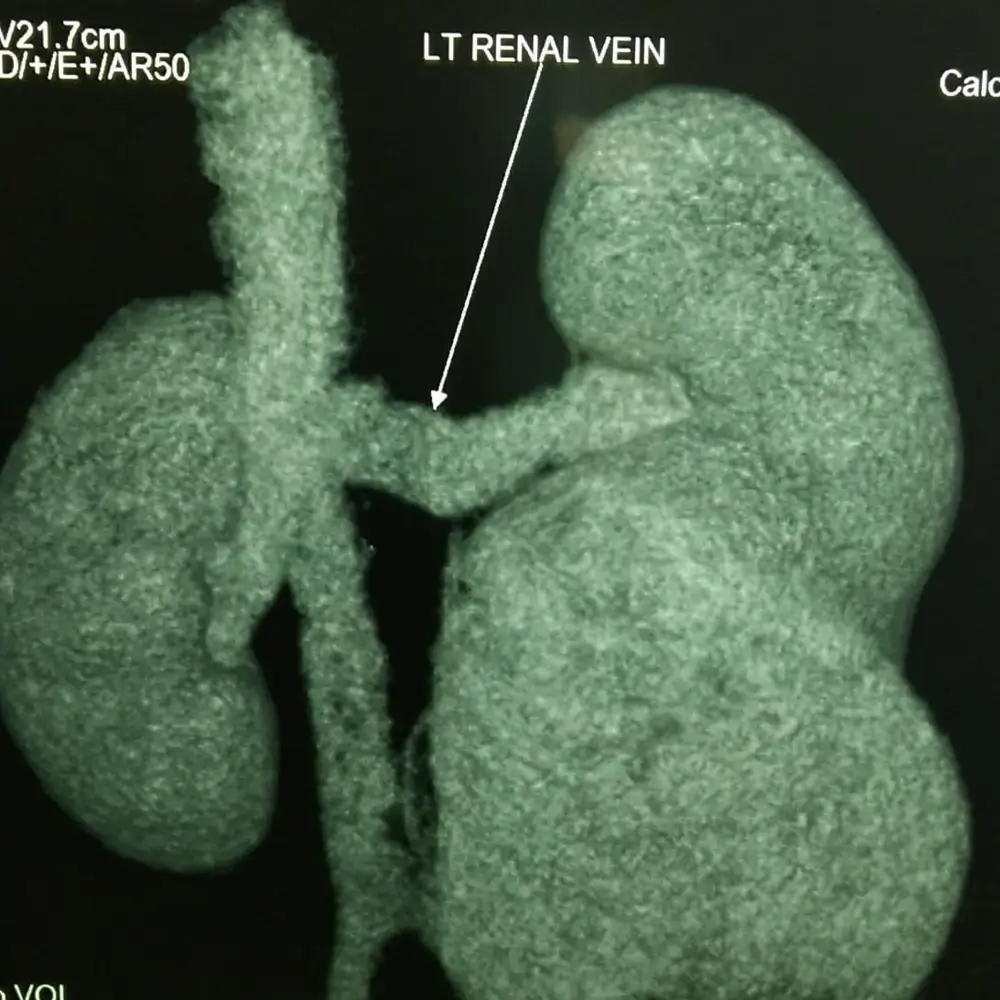

Clinic Procedures Gallery

A visual showcase of advanced urological procedures, highlighting our expertise, technology, and commitment to patient care.